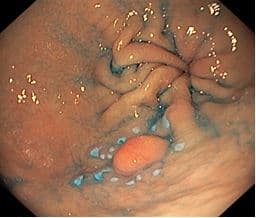

При гастроскопии перед оперативным лечением в нижней трети тела желудка по задней стенке (на границе с большой кривизной) было выявлено эпителиальное новообразование 0-IIa типа размером ~ 15 мм

На рисунке: Осмотр в белом свете. Эндоскоп: GIF Q-150 OLYMPUS. EXERA III. Эпителиальное новообразование 0-IIa типа размером ~ 15 мм.

В центральном отделе желудка по задней стенке, ближе к большой кривизне, определяется эпителиальное новообразование 0-IIa типа диаметром до 15-20 мм, при хромоскопии с 0,2% раствора индигокарминовым - с четкими контурами, без признаков инвазивного роста.

На рисунке хромоскопия 0,2% раствором индигокарминовогодо лопаток.

Эндоскоп: GIF Q-180 OLYMPUS. EXERA III.

Эпителиальное новообразование 0-IIa типа диаметром до 15-20 мм, при хромоскопии с 0,2% раствора индигокарминовым - с четкими контурами, с углублением в крае.